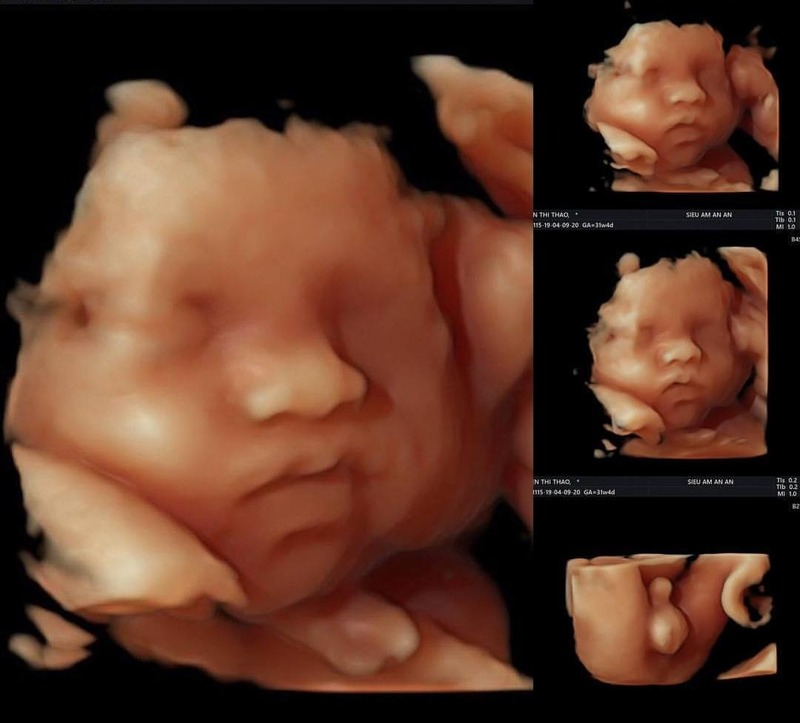

Siêu âm 5D là công nghệ siêu âm hiện đại, cho phép hiển thị hình ảnh thai nhi với độ chi tiết và chân thực cao hơn so với siêu âm 2D, 3D hay 4D. Với siêu âm 5D, bác sĩ có thể quan sát rõ từng bộ phận của thai như gương mặt, chân tay, cột sống hoặc các cơ quan nội tạng. Công nghệ này sử dụng ánh sáng và màu sắc để tái tạo hình ảnh sống động, gần giống như ảnh thật. Ngoài ra, siêu âm 5D còn hỗ trợ phát hiện sớm các dị tật bẩm sinh ở giai đoạn sớm của thai kỳ. Nhờ đó, bố mẹ có thể theo dõi sự phát triển của con một cách trực quan và an tâm hơn.

Siêu âm 5D mang đến hình ảnh sắc nét và chân thực, giúp bố mẹ dễ dàng quan sát thai nhi cũng như hỗ trợ bác sĩ chẩn đoán chính xác các bất thường về hình thái. Tuy nhiên, công nghệ này có chi phí cao hơn so với các phương pháp siêu âm truyền thống và không phải cơ sở y tế nào cũng được trang bị máy siêu âm 5D. Ngoài ra, siêu âm 5D chỉ là phương pháp hỗ trợ, không thay thế được siêu âm 2D trong việc đánh giá chuyên sâu. Bảng so sánh ưu điểm và nhược điểm của siêu âm 5D: